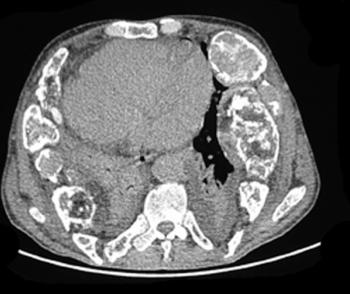

Can you diagnose this mostly asymptomatic patient but with weight loss and abdominal discomfort?